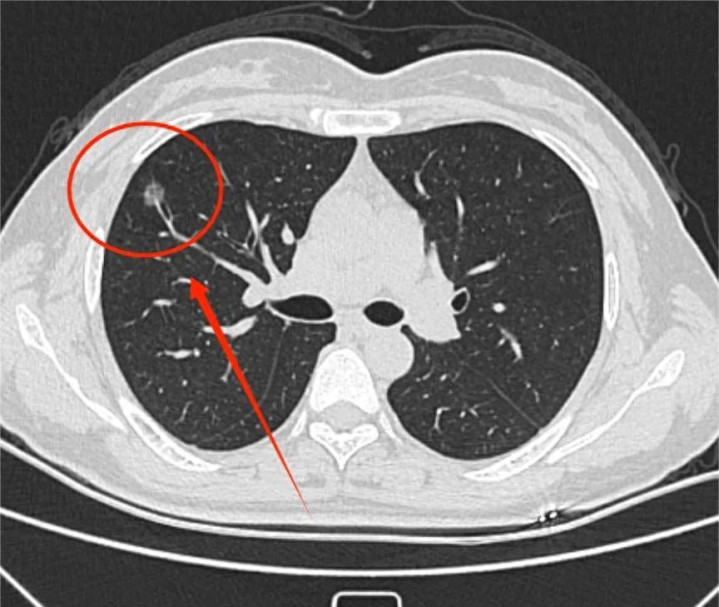

前几天门诊上有这样一个患者:2025年11月体检的时刻发现的双肺多发肺结节,最大的位于右肺下叶,直径6mm纯磨玻璃结节。因为风险尚低,是以医陌生远随访,时刻自愿体魄虚,就自行买了东说念主参、鹿茸进补,近1个月出现口干舌燥、大便干结等问题。2月底复查CT时:原6mm结节增大至8mm,且出现2mm的实性因素,密度增高。